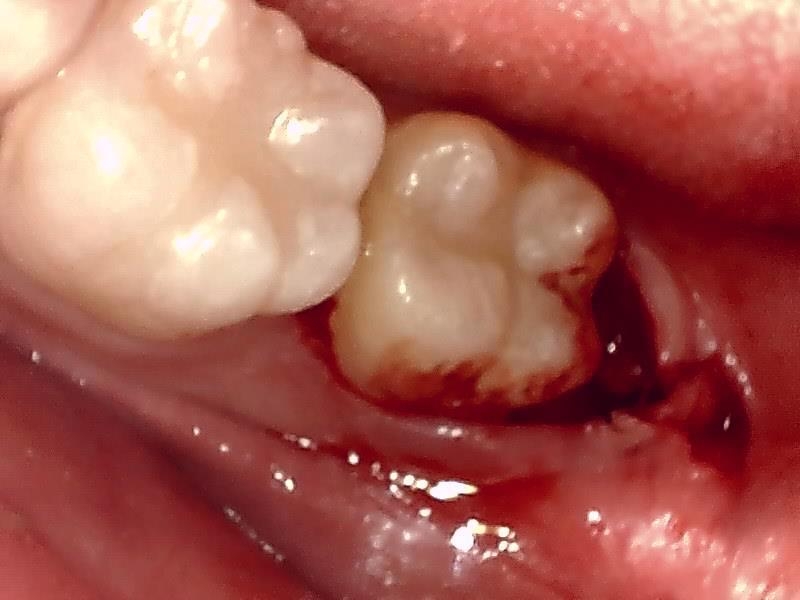

(左下)抜歯窩

切開して歯肉剝離する。

歯牙分割して抜歯する。

縫合

当院では、傷口は最小限に、骨は極力削らずに行います。

骨が歯を覆っているケース以外は骨を削ることはありません。

親知らずのみにアプローチし歯を分割し最小限の傷口で取り出します。

歯肉を切開し、歯が見えるようにして、

周辺の骨を削らないように親知らずを分割し抜きやすくしていきます。

この抜歯法により術後の腫れ痛みが大幅に軽減されます。

抜歯後、経過良好です。